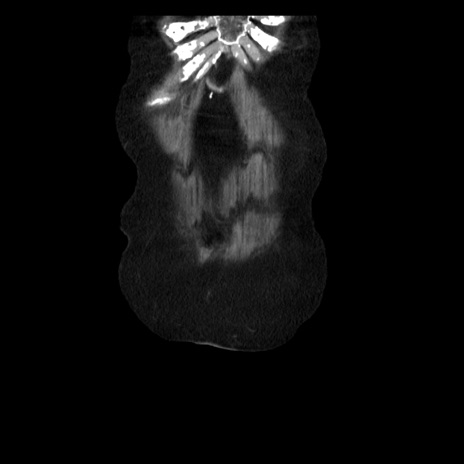

横断像